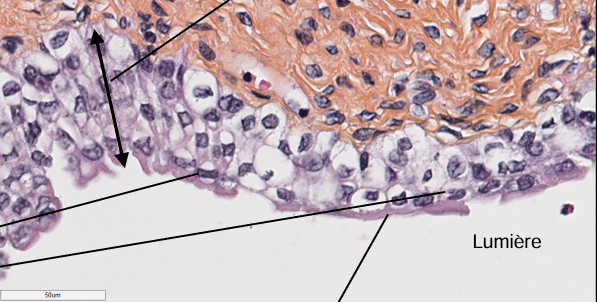

L’image représente quelle type de cellule

Épithélium stratifié pavimenteux malpighien non kératinisé

Q

On regarde les cellules en superficie

11

Ou est la lame basale dans cette image

la ligne entre le rose pale et foncée